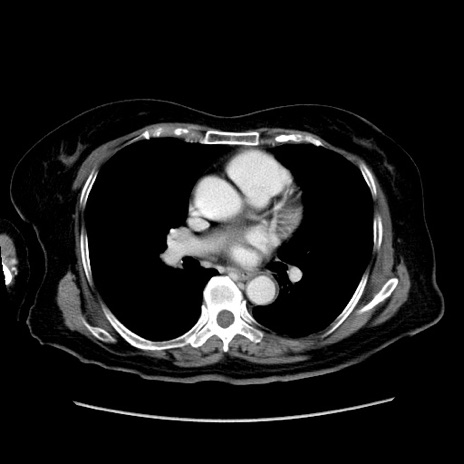

冠状断像

【症例】80歳代女性

【主訴】下腹部痛

【現病歴】約8時間前より下腹部痛の出現あり、救急外来受診。

【既往歴】両側付属器切除

【身体所見】意識清明、下腹部正中に手術痕あり、その部位に一致して圧痛と反跳痛あり。腸蠕動音は亢進。

【データ】WBC 9300、CRP 0.15